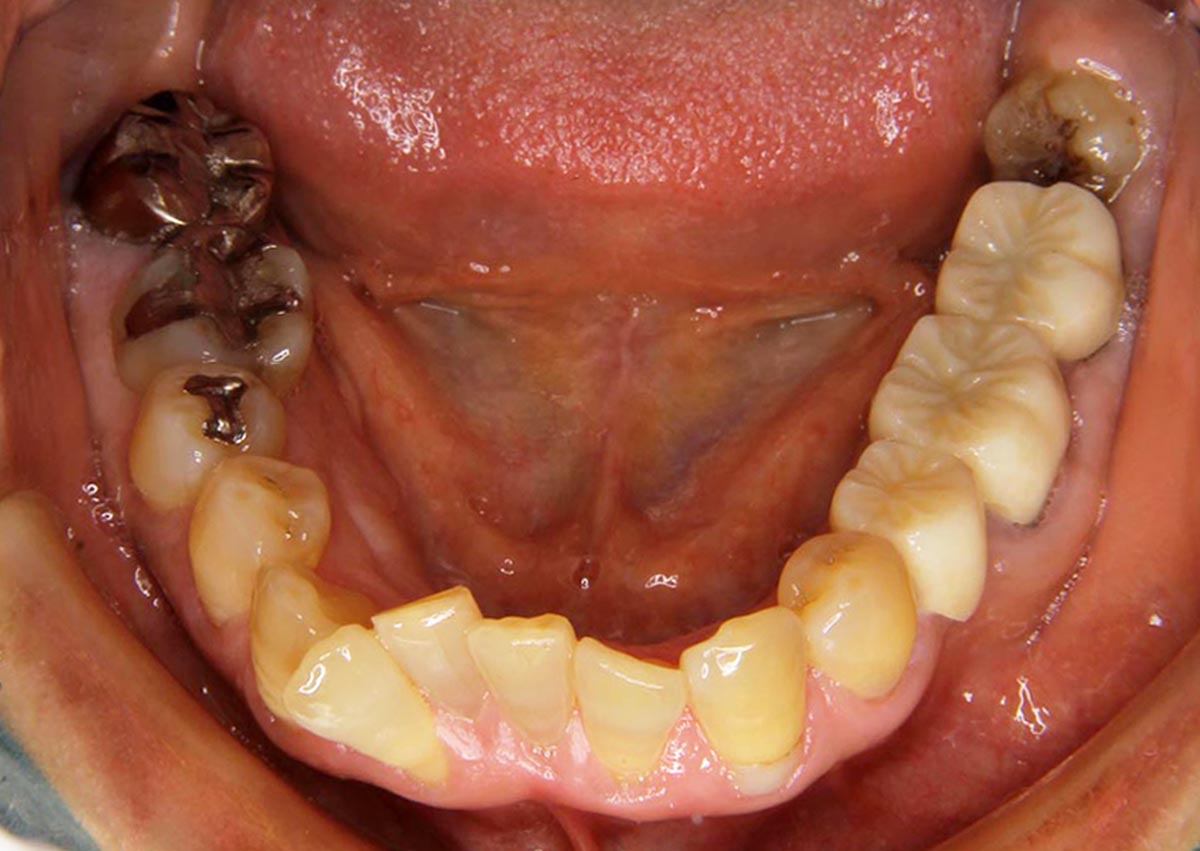

叢生(デコボコ)症例

●主訴

歯のデコボコが気になる

●診断

AngleⅠ級・前歯部叢生

●治療に用いた主な装置

上下顎にマルチブラケット(表側装置)

●抜歯部位

上下左右第一小臼歯4本

●治療期間

2年6ヶ月

●治療費用

約92万円(ともに税込、調整費、保定費まで含む総額制)

●付記

デコボコがきつかったので抜歯症例となりました。

リスクとして、

①歯根吸収…今回は全くありませんでした。

②カリエス(むし歯)…今回は治療途中でむし歯治療を行いました。

③あともどり…保定装置の装着をしっかりしていただいています。